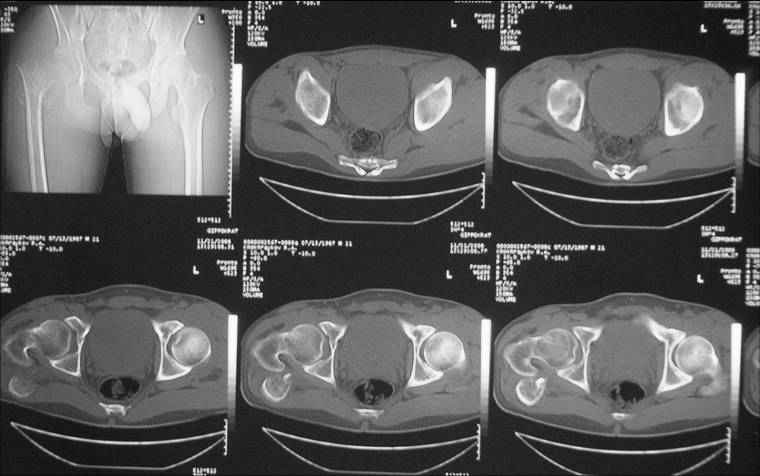

Уважаемые коллеги! Нужен совет.Больной Х., 21 год, ДЗ: ложный сустав вертельной области правого бедра.

Травма 8 мес. назад, ДТП, получил закрытый межвертельный перелом правого бедра. Лечился в городской больнице одного из городов-спутников г. Караганды скелетным вытяжением в течение 3 недель, затем кокситной гипсовой повязкой 2 мес. В настоящее время имеется укорочение конечности на 7 см, умеренная боль в вертельной области; ходит без костылей, полностью нагружая больную конечность, при нагрузке отмечается смещение дистального отломка проксимально примерно на 1,0 см.; объем движений в коленном суставе сохранен; при пальпации отломков боли нет, умеренная патологическая подвижность. Планируем внеочаговый остеосинтез спице-стержневым аппаратом, дистракция до восстановления длины бедра, вторым этапом остеосинтез стержнем Гамма. Есть надежда, что на дистракции пойдет сращение и у больного хватит терпения завершить лечение в аппарате.

Если судить по снимкам, то укорочение кажеться не критическим, но обьективно и на 3D - укорочение на 6-7 см.